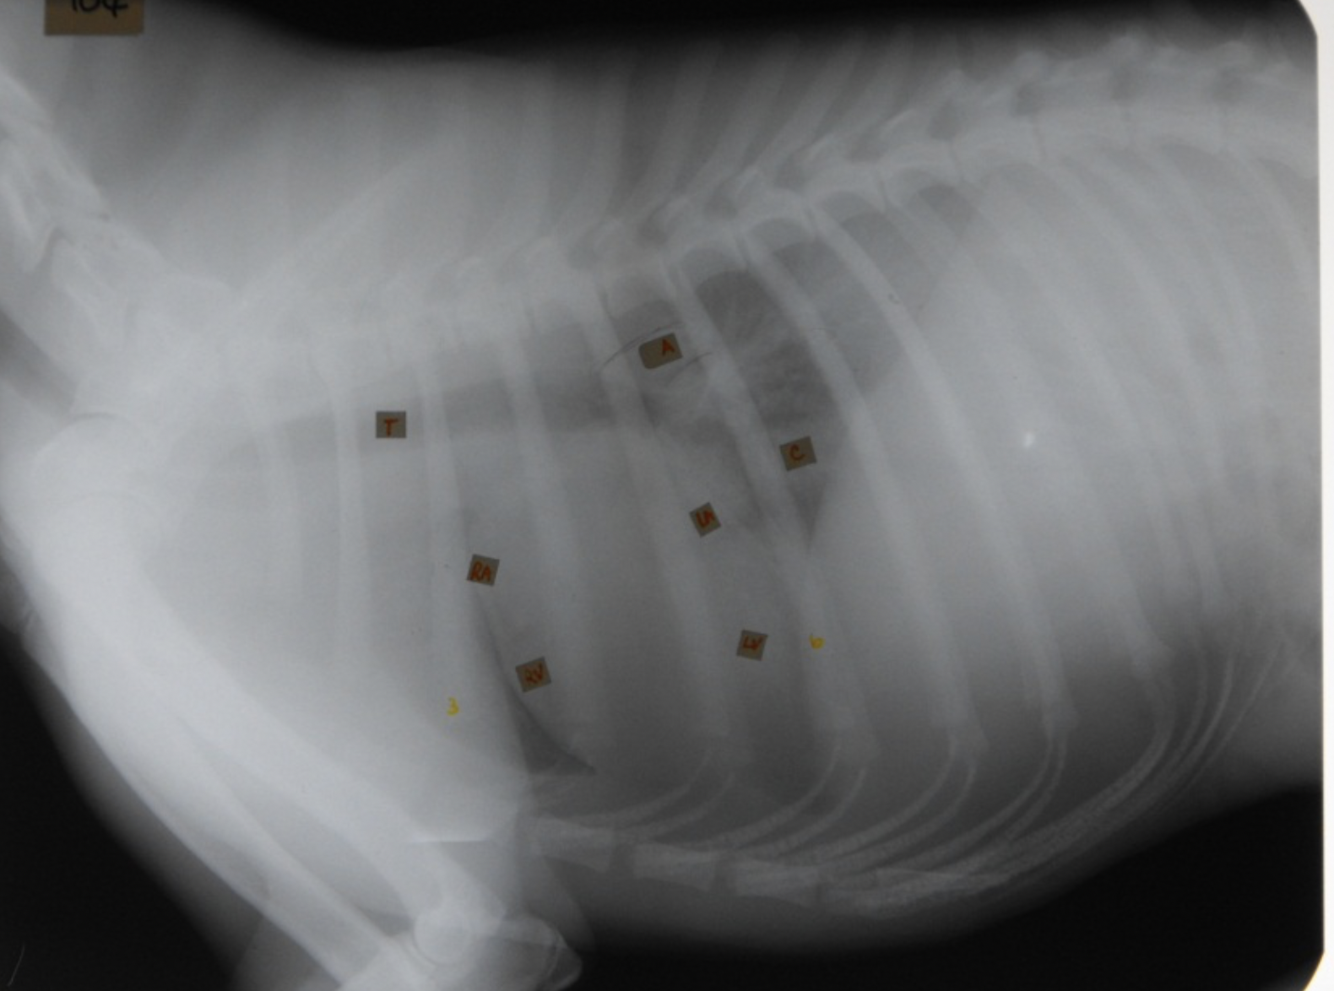

identify the structures

RA: right auricle (atrium)

RV: right ventricle

LV: left ventricle

LA: left atrium

A: aorta

C: caudal vena cava

T: trachea